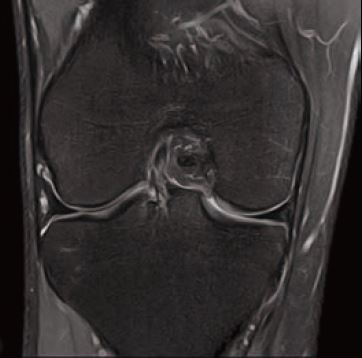

Випадок 1. Велике коліно

Жінка 67 років скаржиться на постійний медіальний біль у коліні.

• Відносно рясний внутрішньосуглобовий випіт.

• Остеоартритне ураження стегново-гомілкового суглоба в медіальній частині зі змінами субхондральної кістки, що може відповідати стресовому перелому.

• Дегенеративна сторона заднього рогу медіального меніска.

Рис. 3 Co FSE PD FS, товщина зрізу 3 мм, роздільна здатність 0,6 мм.